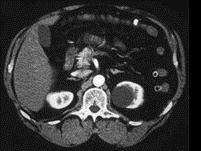

问题 1986年Bosniak根据CT征象提出肾囊性病变四级分类法,下列图片中的肾囊肿属于哪一类 ( )

选项 A、BosniakⅣ类 B、以上都不是 C、BosniakⅡ类 D、BosniakⅢ类 E、BosniakⅠ类

答案 E